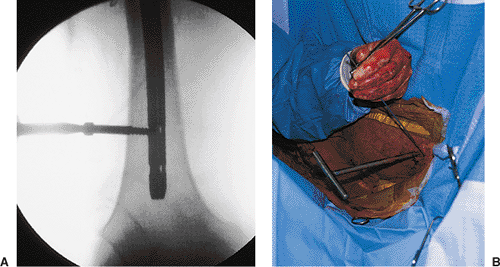

closed intramedullary nailing was performed with a static locked nail.

Because the fracture was mid-diaphyseal, a single distal screw was used

for fixation (Fig. 21.55).

The patient was mobilized on the second postoperative day. The fracture

healed uneventfully in 4 months with excellent restoration of function.

Figure 21.55. Postoperative radiograph.